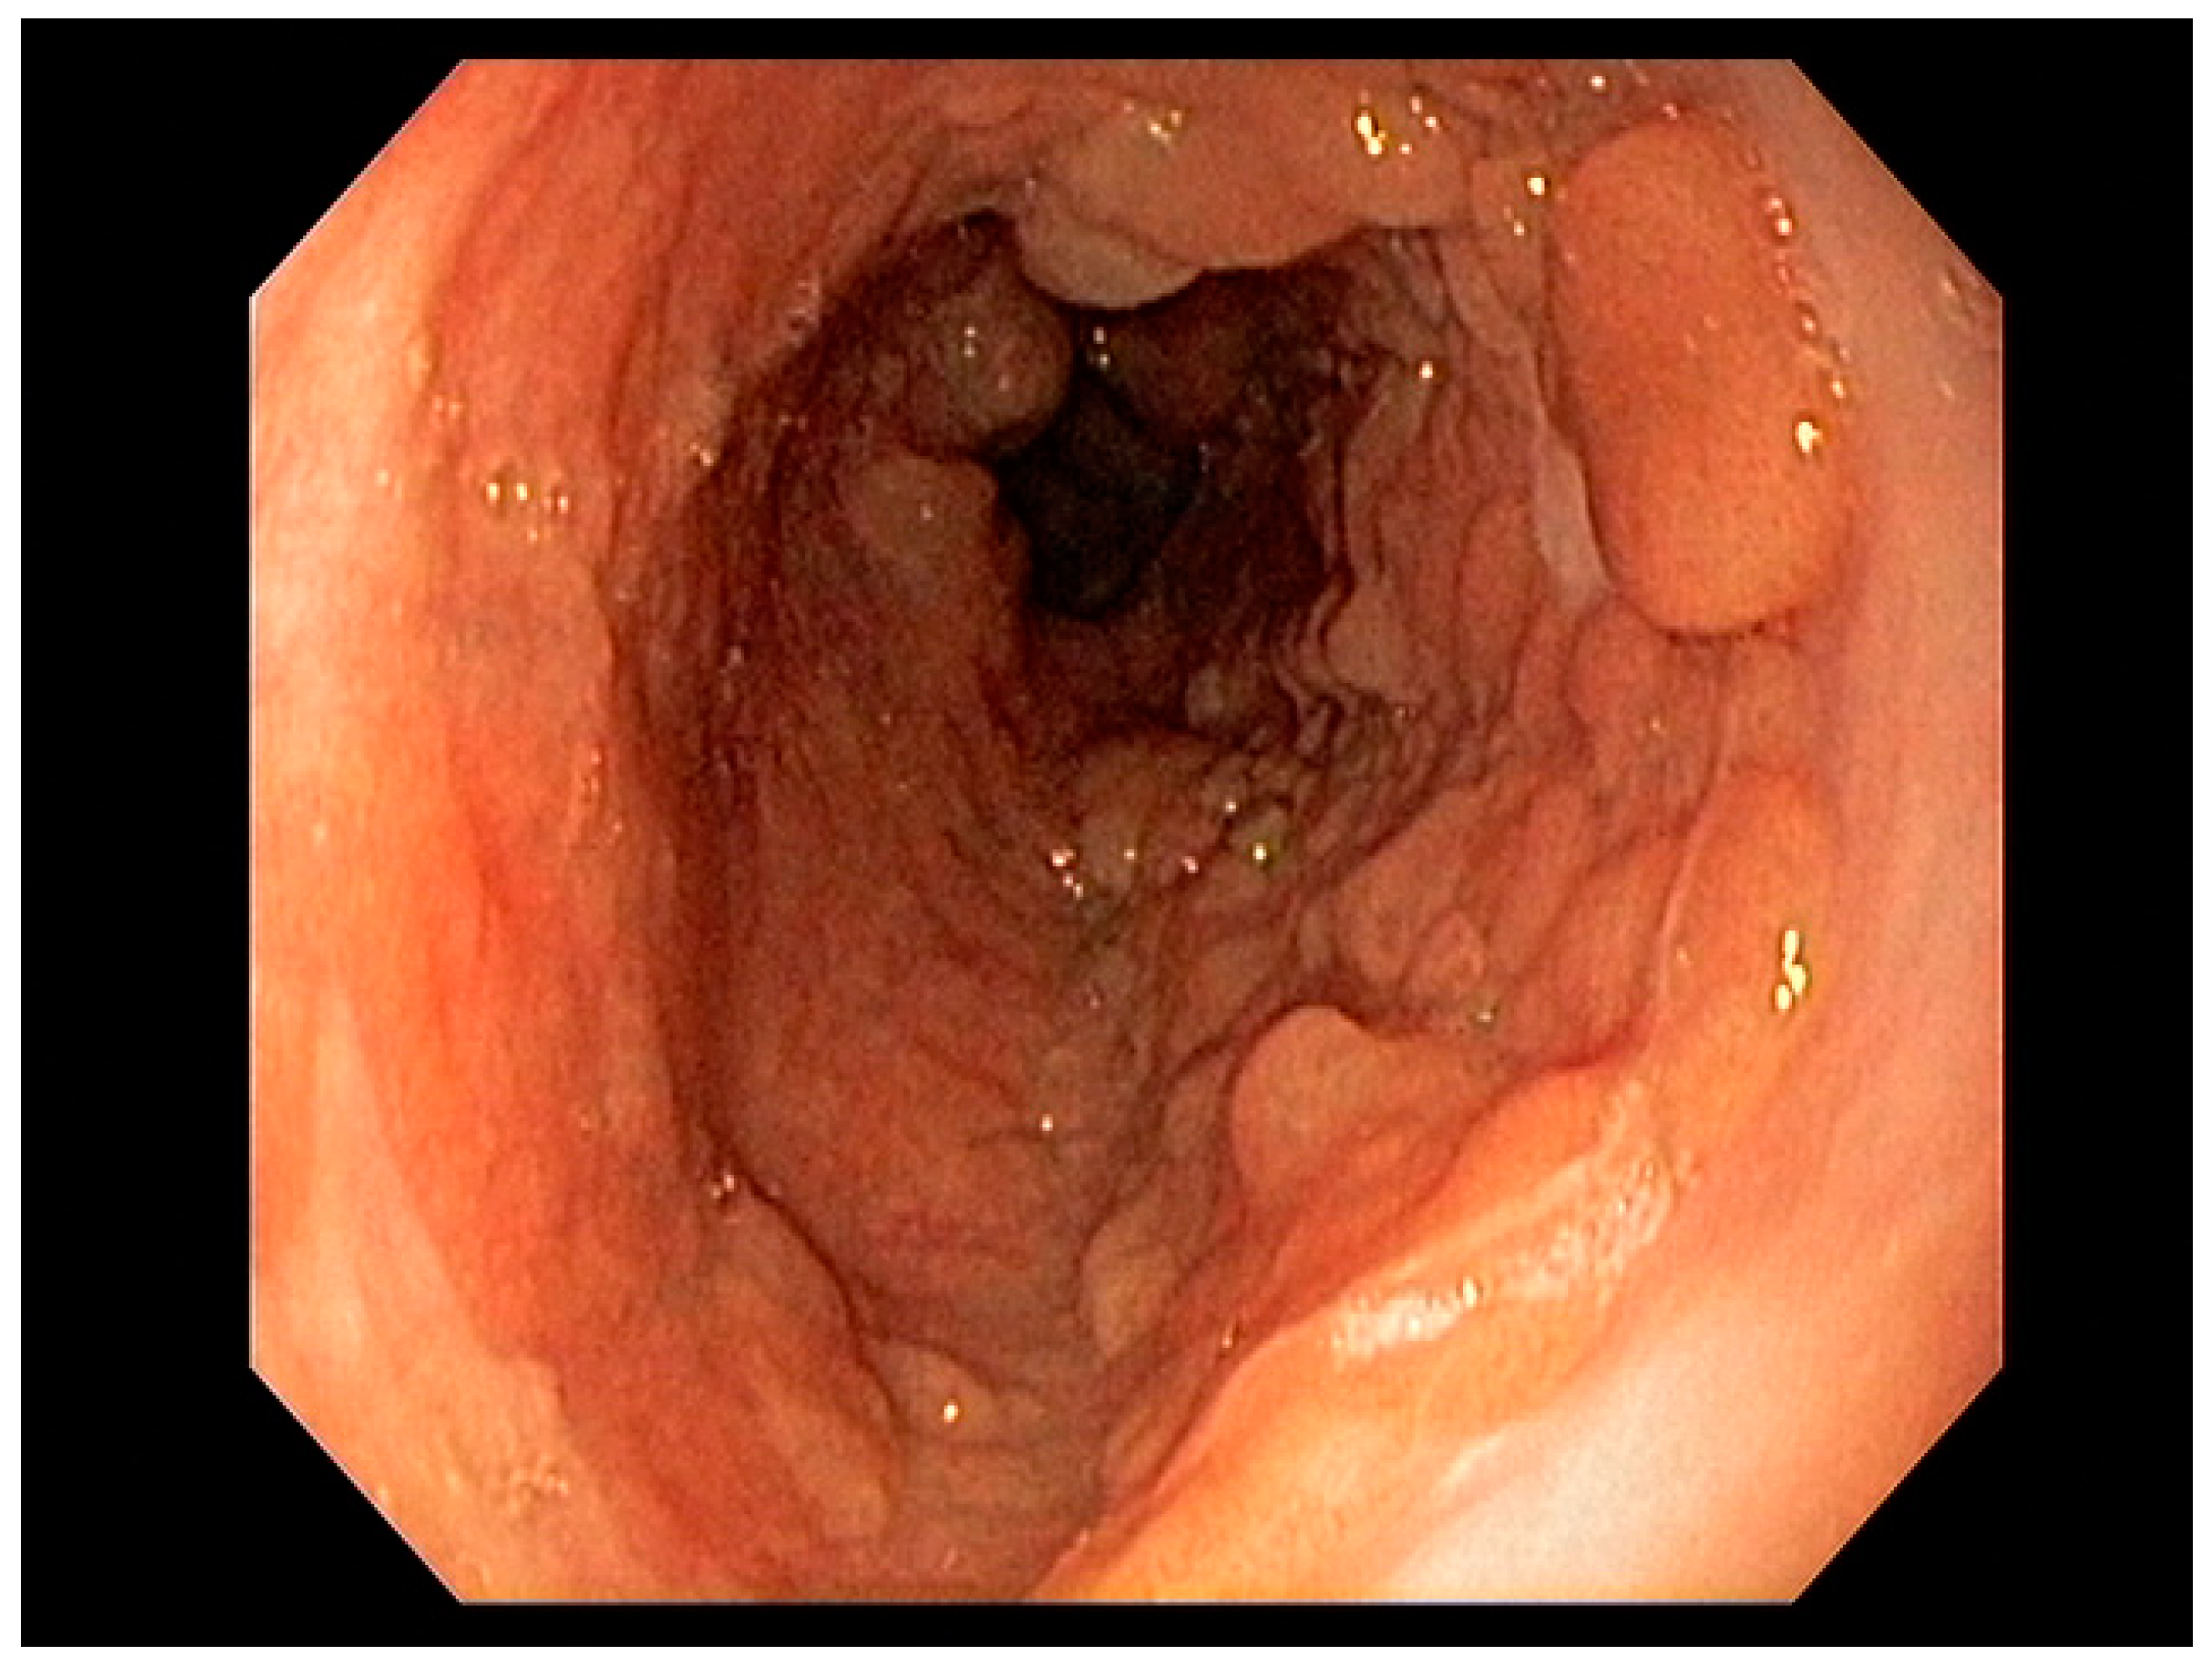

4.2. Early Gastric Cancer (EGC)

- Waddingham, W.; Nieuwenburg, S.A.V.; Carlson, S.; Rodriguez-Justo, M.; Spaander, M.; Kuipers, E.J.; Jansen, M.; Graham, D.G.; Banks, M. Recent advances in the detection and management of early gastric cancer and its precursors. Front. Gastroenterol. 2020. [Google Scholar] [CrossRef]